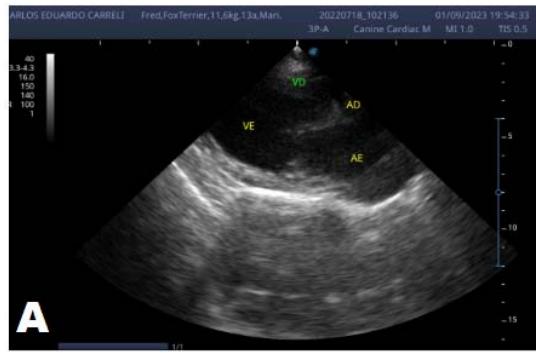

An echocardiogram (ECHO) (Figure 1) showed a thickened mitral valve and enlarged heart chambers. At first was prescribed Pimobendan PO at a dose of $0.25\mathrm{mg/kg}$ BID, continuous use, and requested to return in 30 days.

Figure 1: Echocardiogram 2021: Thickened/degenerated mitral valve (A); Observed in Doppler mode, significant mitral valve insufficiency (B); Hemodynamic assessment - Mitral regurgitation gradient: $3.45 \mathrm{~m} / \mathrm{s} / 47.68 \mathrm{mmHg}$; enlargement of left cardiac chambers; left ventricular diastolic dimension above normal limits was observed

In the reported, he was asymptomatic, and the echocardiographic examination showed enlargement of the left heart chambers, thickened and degenerated mitral valve (Figure 1), left ventricular diastolic dimension above normal limits. with normal systolic function parameters, characterizing systolic dysfunction. The thickening and degeneration of the mitral valve indicates its insufficiency, and the other changes represent diastolic dysfunction.